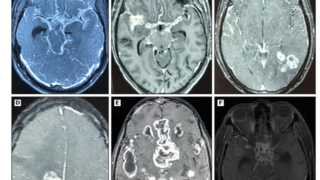

白質病変

CMV、EBV、VZV、JCウイルス

脳梗塞・血管病変

アスペルギルス、クリプトコッカス、ムコール、VZV

Mass病変

ノカルジア、結核、クリプトコッカス、トキソプラズマ、悪性リンパ腫

脳幹病変

リステリア、VZV、JCウイルス、ウェストナイル熱

両側頭葉病変

ヘルペスウイルス、傍腫瘍症候群